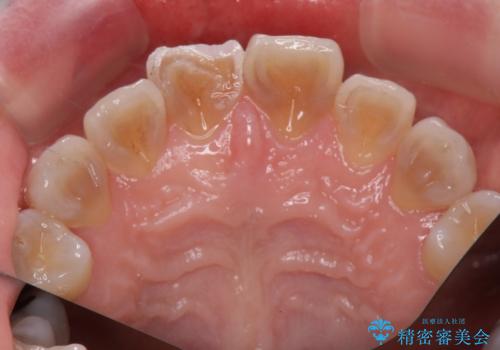

テトラサイクリン歯といって縞模様の強い歯の色調再現を行いました。

まず保険治療でコンポジットレジン修復を行い、神経の状態を確認した後、クラウンによる修復を行いました。